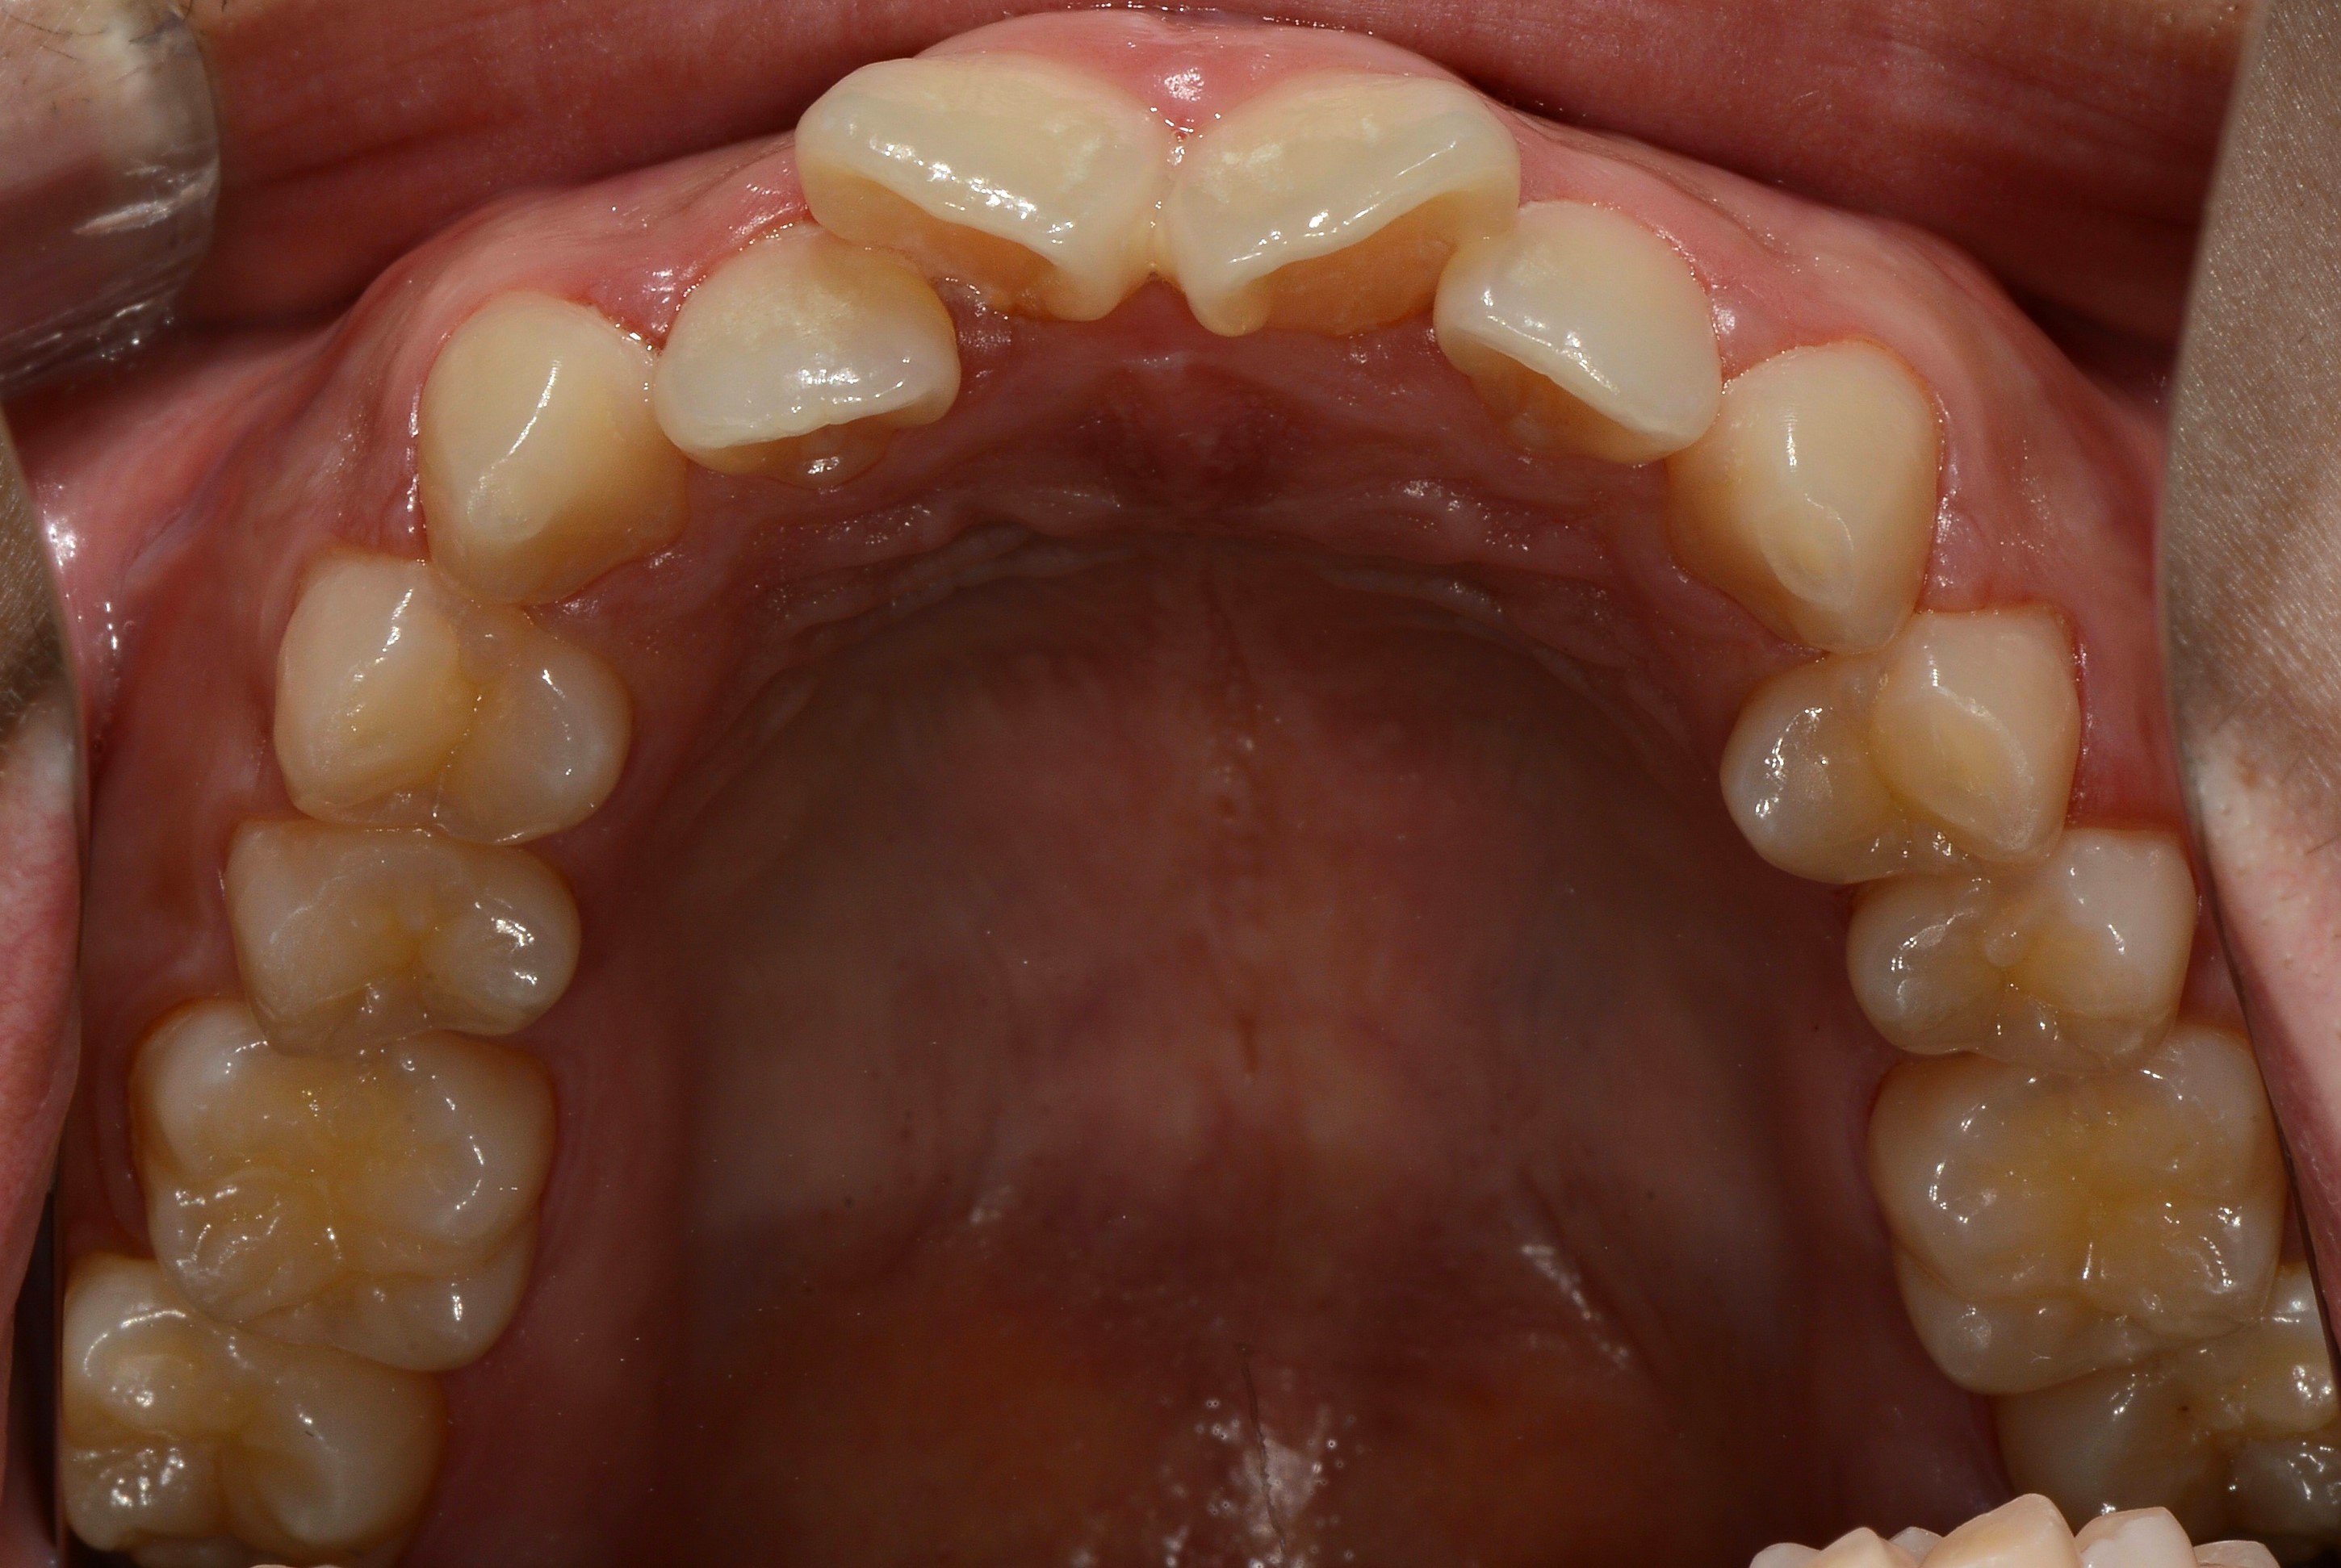

치료 전 사진입니다.